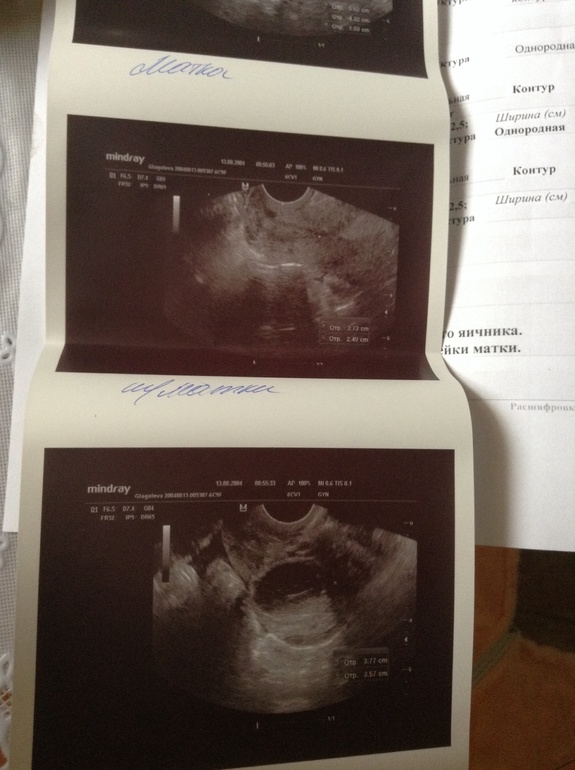

Четвертый день задержки, болит живот, тесты отрицательные. Пришла на узи и на тебе. В яичнике киста ЖТ (у меня такая при Б была) и она сказала, что она начала лопаться! И появилась уже жидкость 30 мл от нее...

Дальше... Что это за анэхогенное включение в матке? Это может быть миома? Или что это? Вот про это включение она мне ни слова не сказала, а увидела я уже когда в машине протокол стала читать. Ну и киста на шм. Короче, вообще ниче непонятно... Сказала половой покой и вообще покой.....

На ПЯ похоже это ваше анэхогенное образование. В самом дне матке как раз. И ЖТ шикарное! Может сдадите кровь на хгч?

Киста жт может и во время б лопнуть... следите за самочувствием если болеть будет! Обращование в матке видно на фото! Если это не б то возможно как и на шейкн типа эндометриозного образования...

На втором фото! Прямо в дне матки!!!!!

Аааа, вижу что то полукруглое... Такое большое.. Спасибо

И вроде не в эндометрии а в миометрии... т.е в мышечном слое матки... как и в шейке... эндометриоз никогда не ставили пож вопросом?

Киста 2,5 на 2,5.... Да у меня тоже она была во время бер. До 15 недель. У меня не бок болит, а живот... Я поэтому на узи и поперлась...